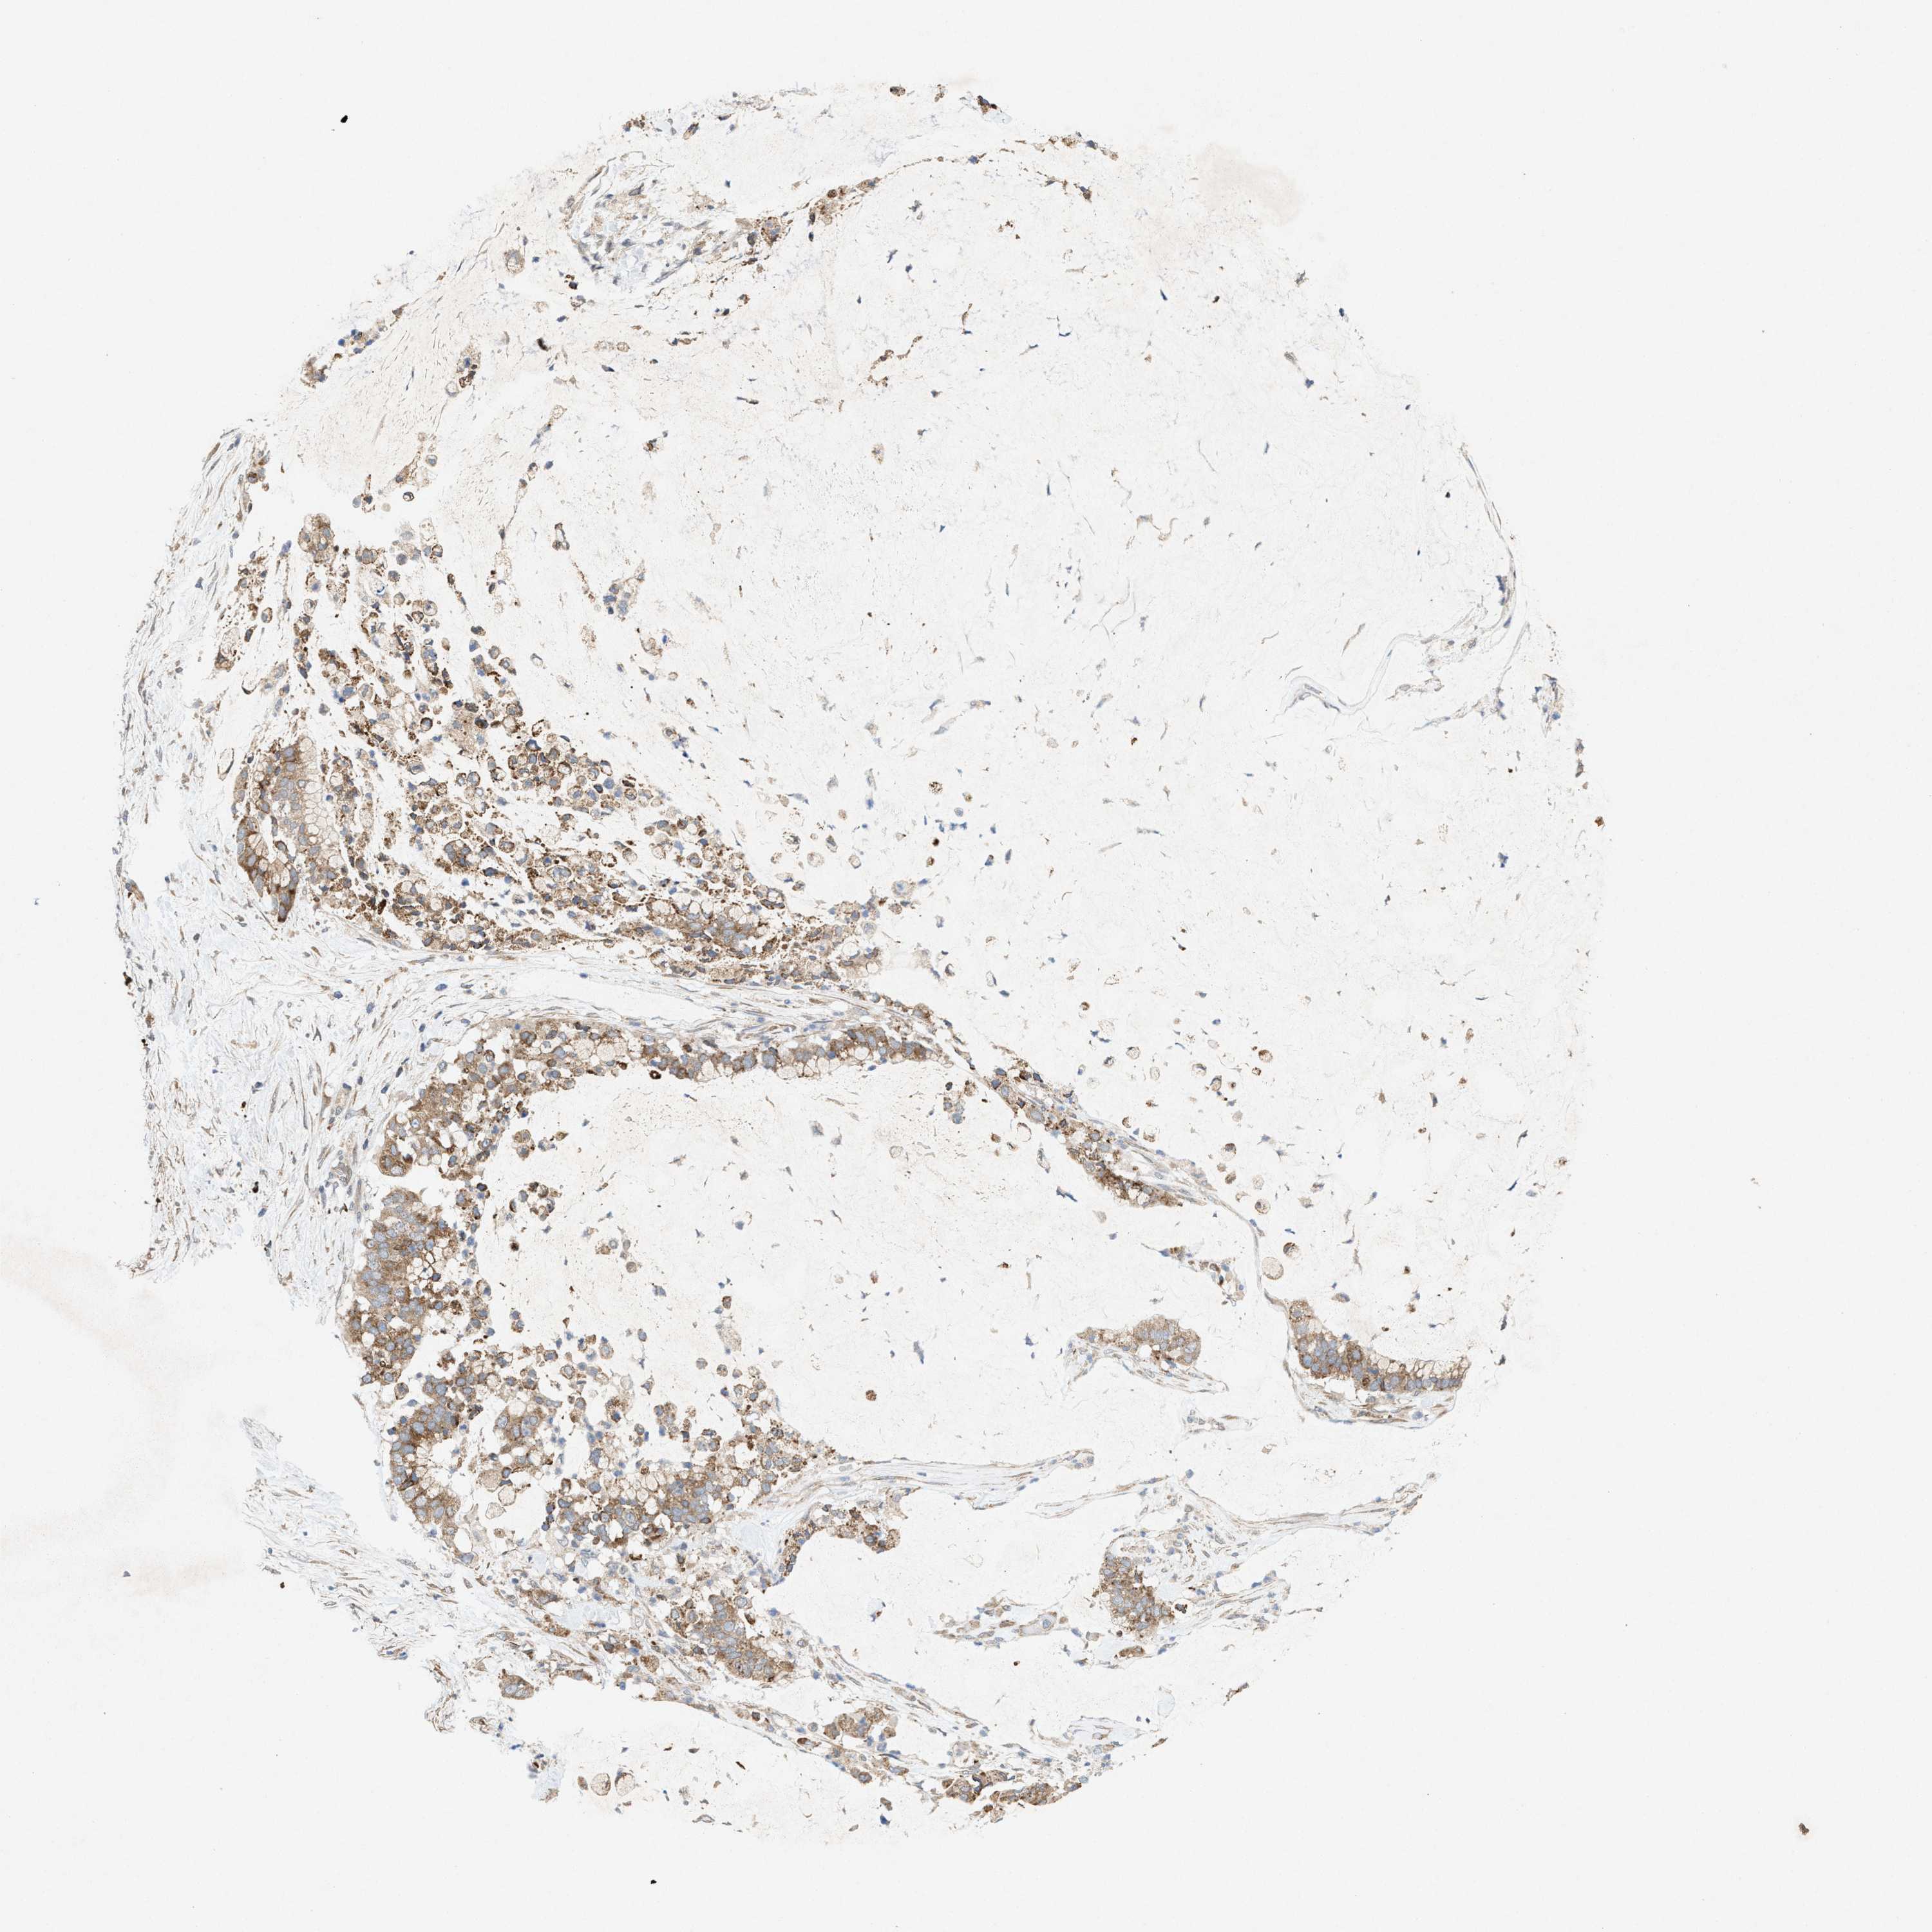

PANCREATIC CANCER - Protein expressioni

A mouse-over function shows sample information and annotation data. Click on an image to view it in a full screen mode. Samples can be filtered based on level of antibody staining by selecting one or several of the following categories: high, medium, low and not detected. The assay and annotation is described here.

Note that samples used for immunohistochemistry by the Human Protein Atlas do not correspond to samples in the TCGA dataset.

Antibody stainingi

Antibody staining in the annotated cell types in the current human tissue is reported as not detected, low, medium, or high, based on conventional immunohistochemistry profiling in selected tissues. This score is based on the combination of the staining intensity and fraction of stained cells.

Each image is clickable and will lead to virtual microscopy that enables deeper exploration of all samples and also displays staining intensity scores, fraction scores and subcellular localization as well as patient and tissue information for each sample.

Antibody HPA022274

Staining

High

Medium

Low

Not detected

Intensity

Strong

Moderate

Weak

Negative

Quantity

>75%

75%-25%

<25%

None

Location

Nuclear

Cytoplasmic/membranous

Cytoplasmic/membranous,nuclear

Adenocarcinoma, NOS